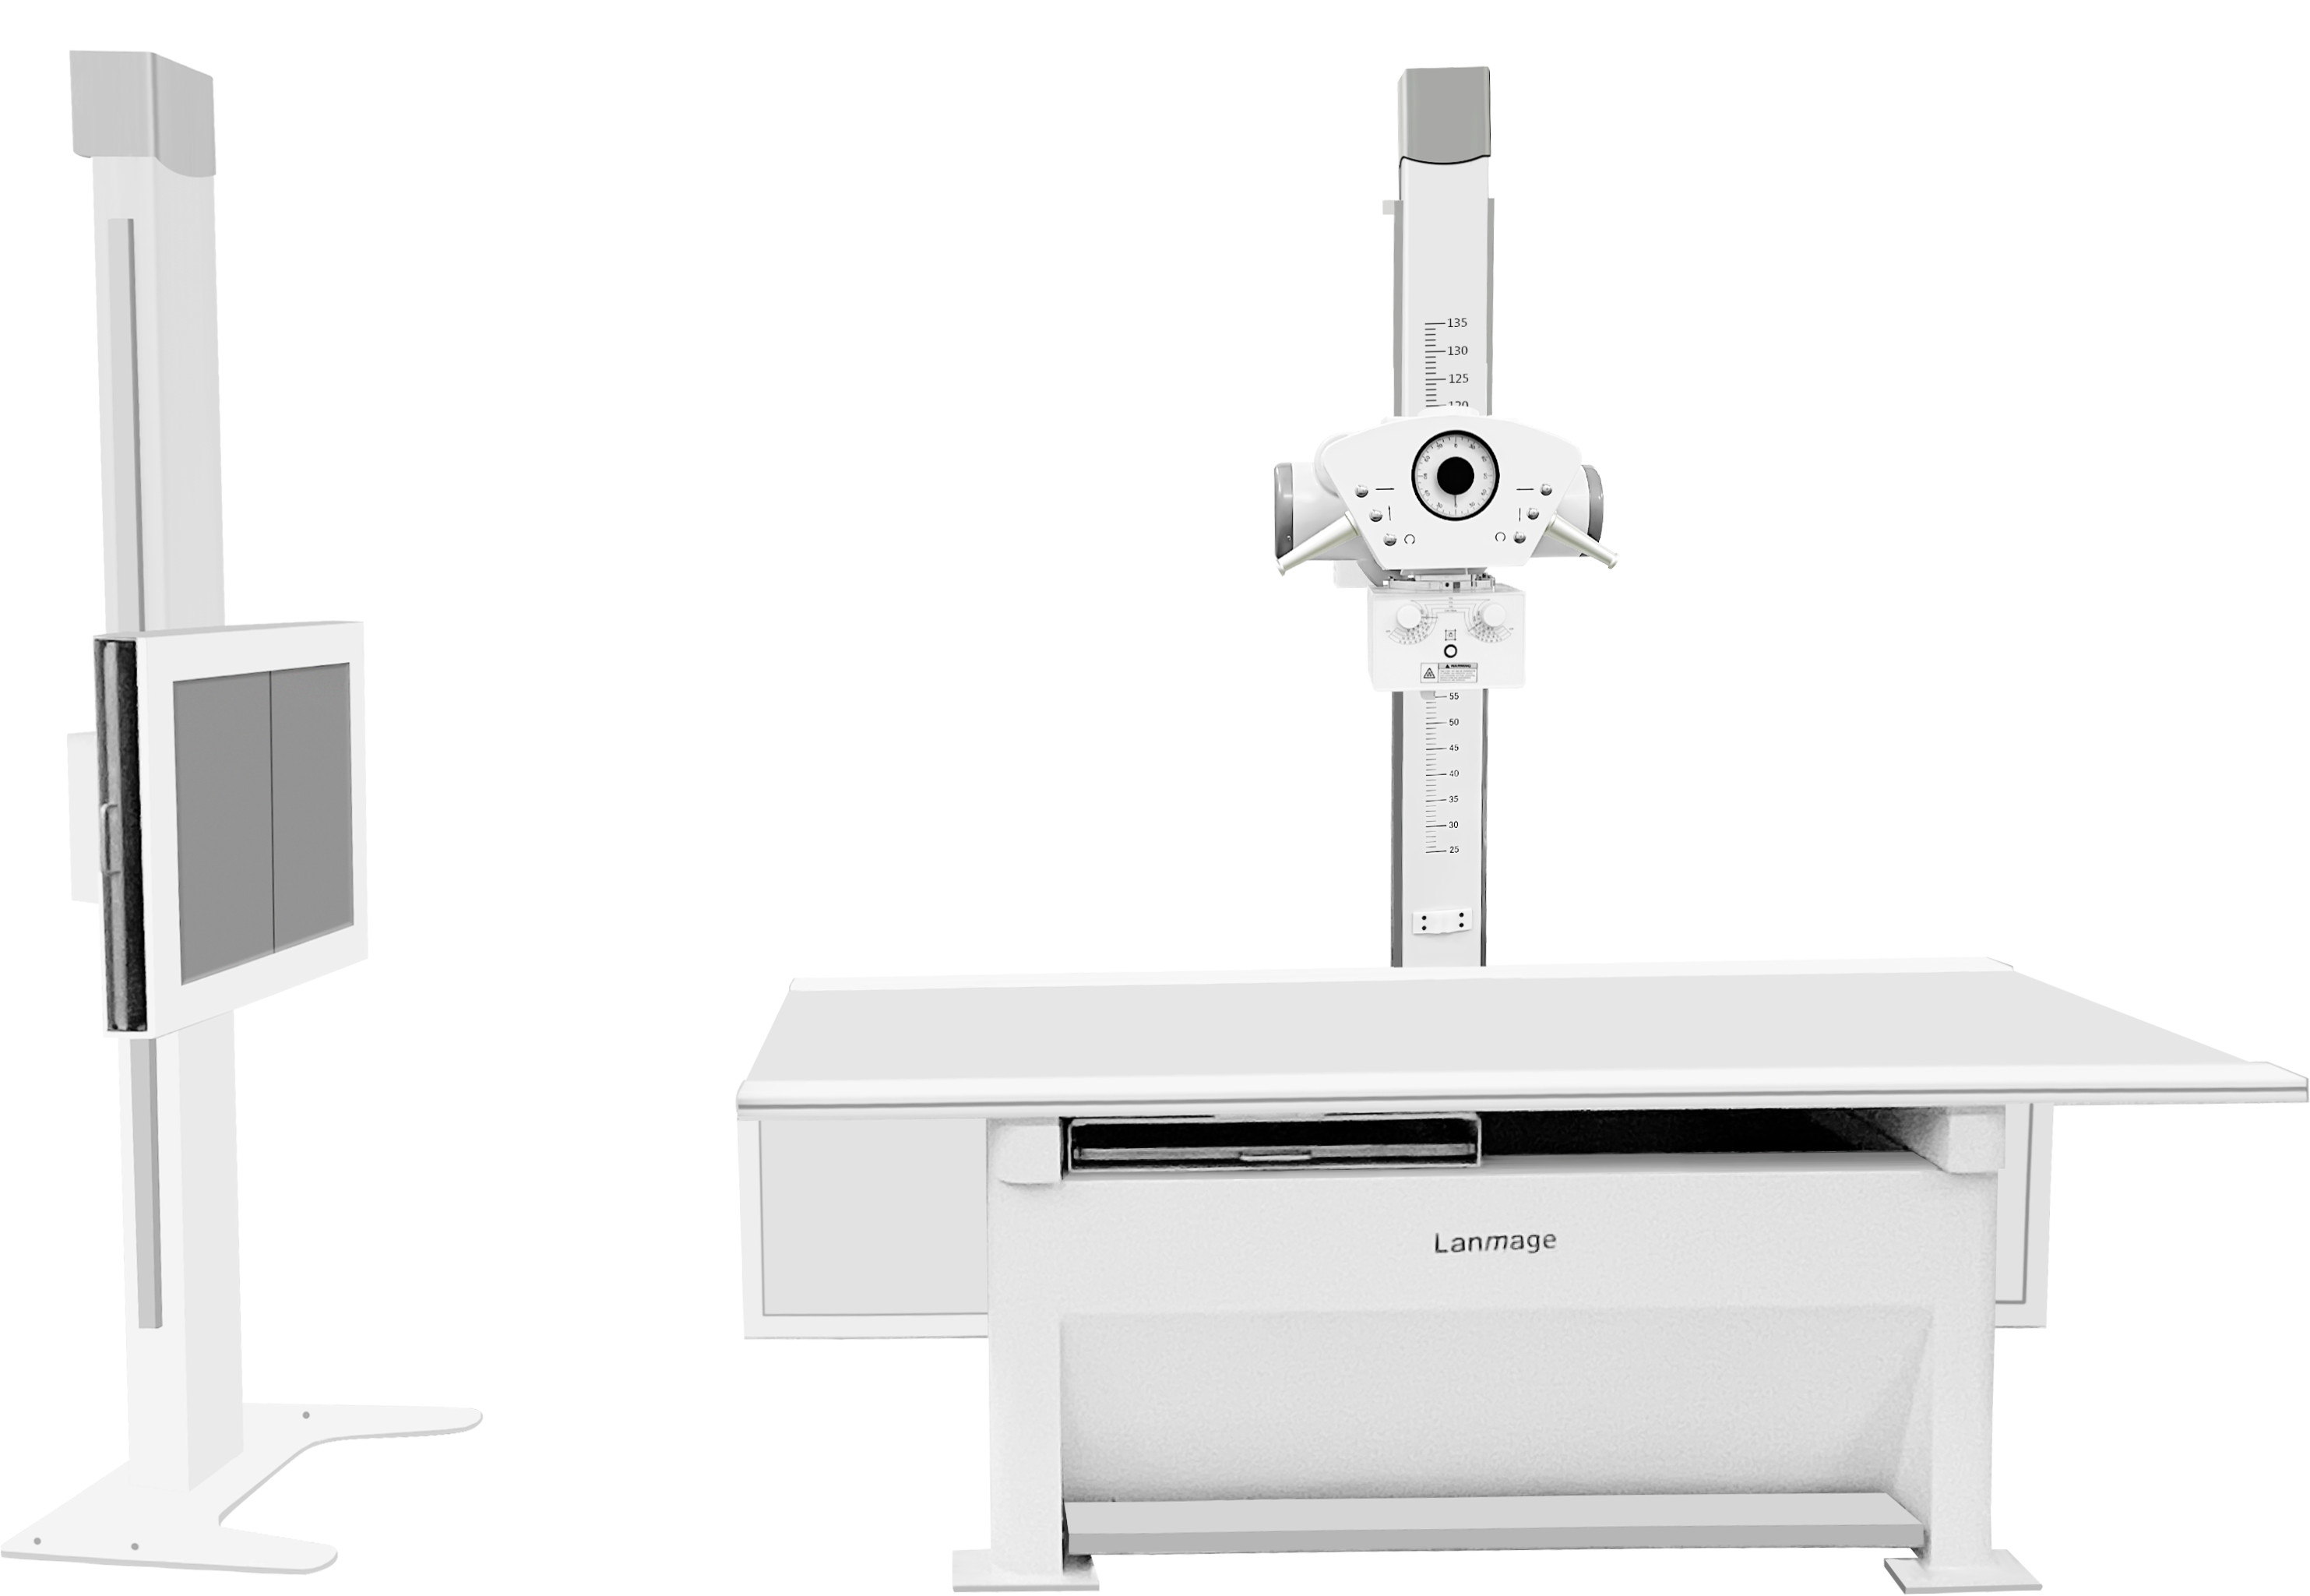

Lanmage propose des systèmes d’imagerie médicale avancés, combinant haute performance et technologies modernes pour offrir des images précises et un diagnostic fiable dans divers domaines de la radiologie.